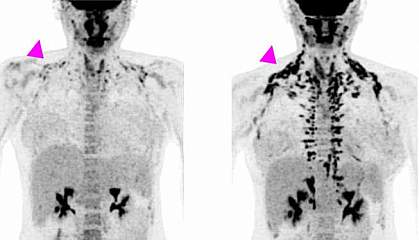

Brown Fat Research and Cancer

Exciting new findings published in the journal Nature show great promise in the treatment of cancer by activating brown fat. (Seki, T., Yang, Y., Sun, X. et al. Brown-fat-mediated tumour suppression by cold-altered global metabolism. Nature 608, 421–428 (2022)). Energy is needed by the majority of cancers to fuel their out-of-control growth. Tumors use glucose and need a lot of it. Brown fat that is active is also fueled by glucose. In a study of rodents and a test study of a human, scientists found that brown fat activated by mild cold "competed" with cancer cells for glucose and slowed the growth of tumors. This effect even included untreatable cancers such as pancreatic cancer. The research opens the door to a new field of study for effective treatment of cancers by using cold exposure or other approaches to activate brown fat to treat cancer.